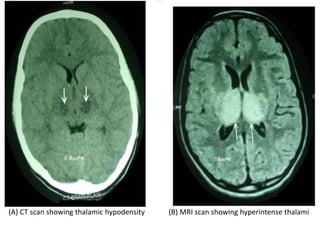

NEUROIMAGING

(A) CT scan showing thalamic hypodensity (B) MRI scan showing hyperintense thalami

(A) CT scanshowing thalamic hypodensity (B) MRI scan showing hyperintense thalami

• #23 xial T2-weighted image shows bilateral thalamic and basal ganglia lesions (black arrows). Note left-sided insular involvement (white arrow).